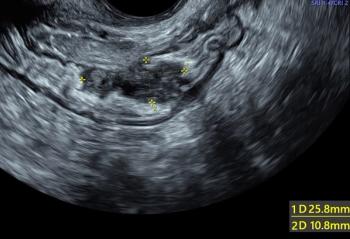

The first slideshow of our gynecologic ultrasound collection reviews commonly missed diagnoses and offers tips for recognizing them on ultrasound.

Early imaging is key to the diagnosis of the many anomalies that are unique to multifetal gestations. The third slideshow of our ultrasound collection includes examples of these anomalies.

While several fetal anomalies can be diagnosed early in the pregnancy, second-trimester ultrasound can identify or exclude even more conditions. The second slideshow of our ultrasounds collection includes the second-trimester anomalies of the body and limbs that shouldn't be missed.

Ultrasound imaging is a key prenatal tool for revealing structural anomalies that may point to genetic conditions. This slideshow is Part 1 of our collection of ultrasound anomalies and includes first-trimester anomalies and second-trimester anomalies of the head and brain. Part 2 will discuss second-trimester anomalies of the body and limbs.